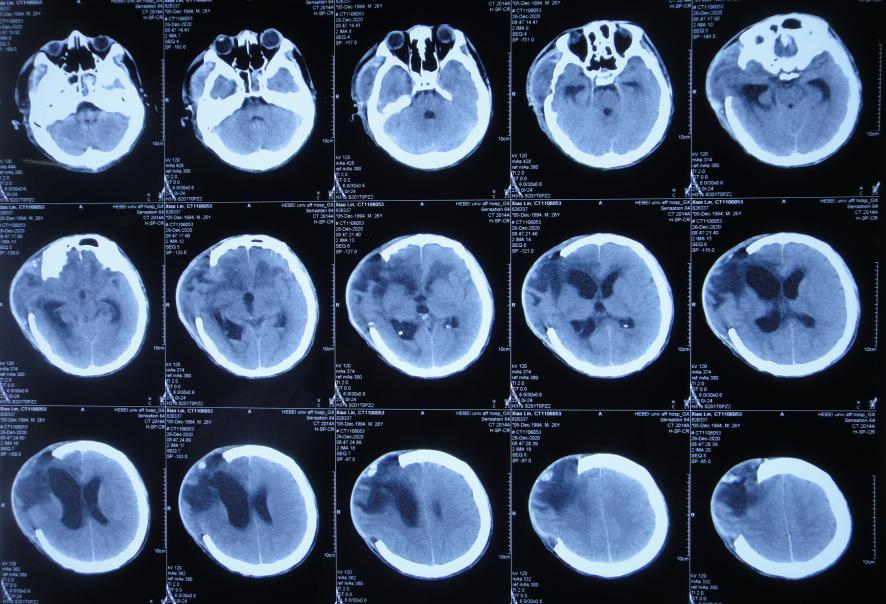

患者于2020年12月12日,在工作时意外从货车上摔下致头颅受伤,出现意识不清,送至河北省定兴县某医院,急诊查头颅CT示颅内血肿,中线有偏移( 图-1 ),给予开颅颅内血肿清除术+去骨瓣减压术,留置引流管,并行气管切开术;术后当天查头颅CT示开颅术后状态( 图-2 ),转入ICU病房。

图-2: 2020年12月12日开颅术后头颅CT